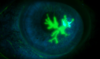

Why is there cupping in chronic glaucoma?

Normal optic cup is <0.5 the size of the optic disc.

When there is an increased pressure in the eye this puts pressure on the cup making it wider and deeper so >0.5 the size of the optic disc

Loss of disc makes the cup look larger